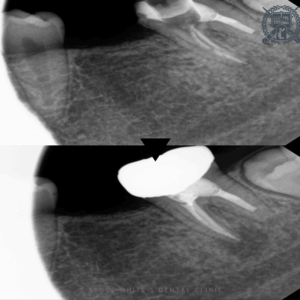

영도치과, 치료받은 곳이 다시 아파요! 재근관치료 사례 안녕하세요 영도치과 서울화이트S치과입니다. 치료를 받았던 치아가 시간이 지나 다시 아프기 시작하면, 당혹스러움과 함께 걱정도 커지기 마련입니다. 이미 신경치료를 한 치아에서 통증이 재발했다면,…